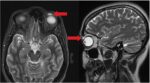

まぶたの裏にコンタクト27枚収納事件

レス10番の画像1

レス10番の画像2

こいつでも生きてるんだし大丈夫だよね?

>>10

これ外科手術ならイッチも手術になるんかね?

枚数違うとは言えたぶん起こったことは同じやろ